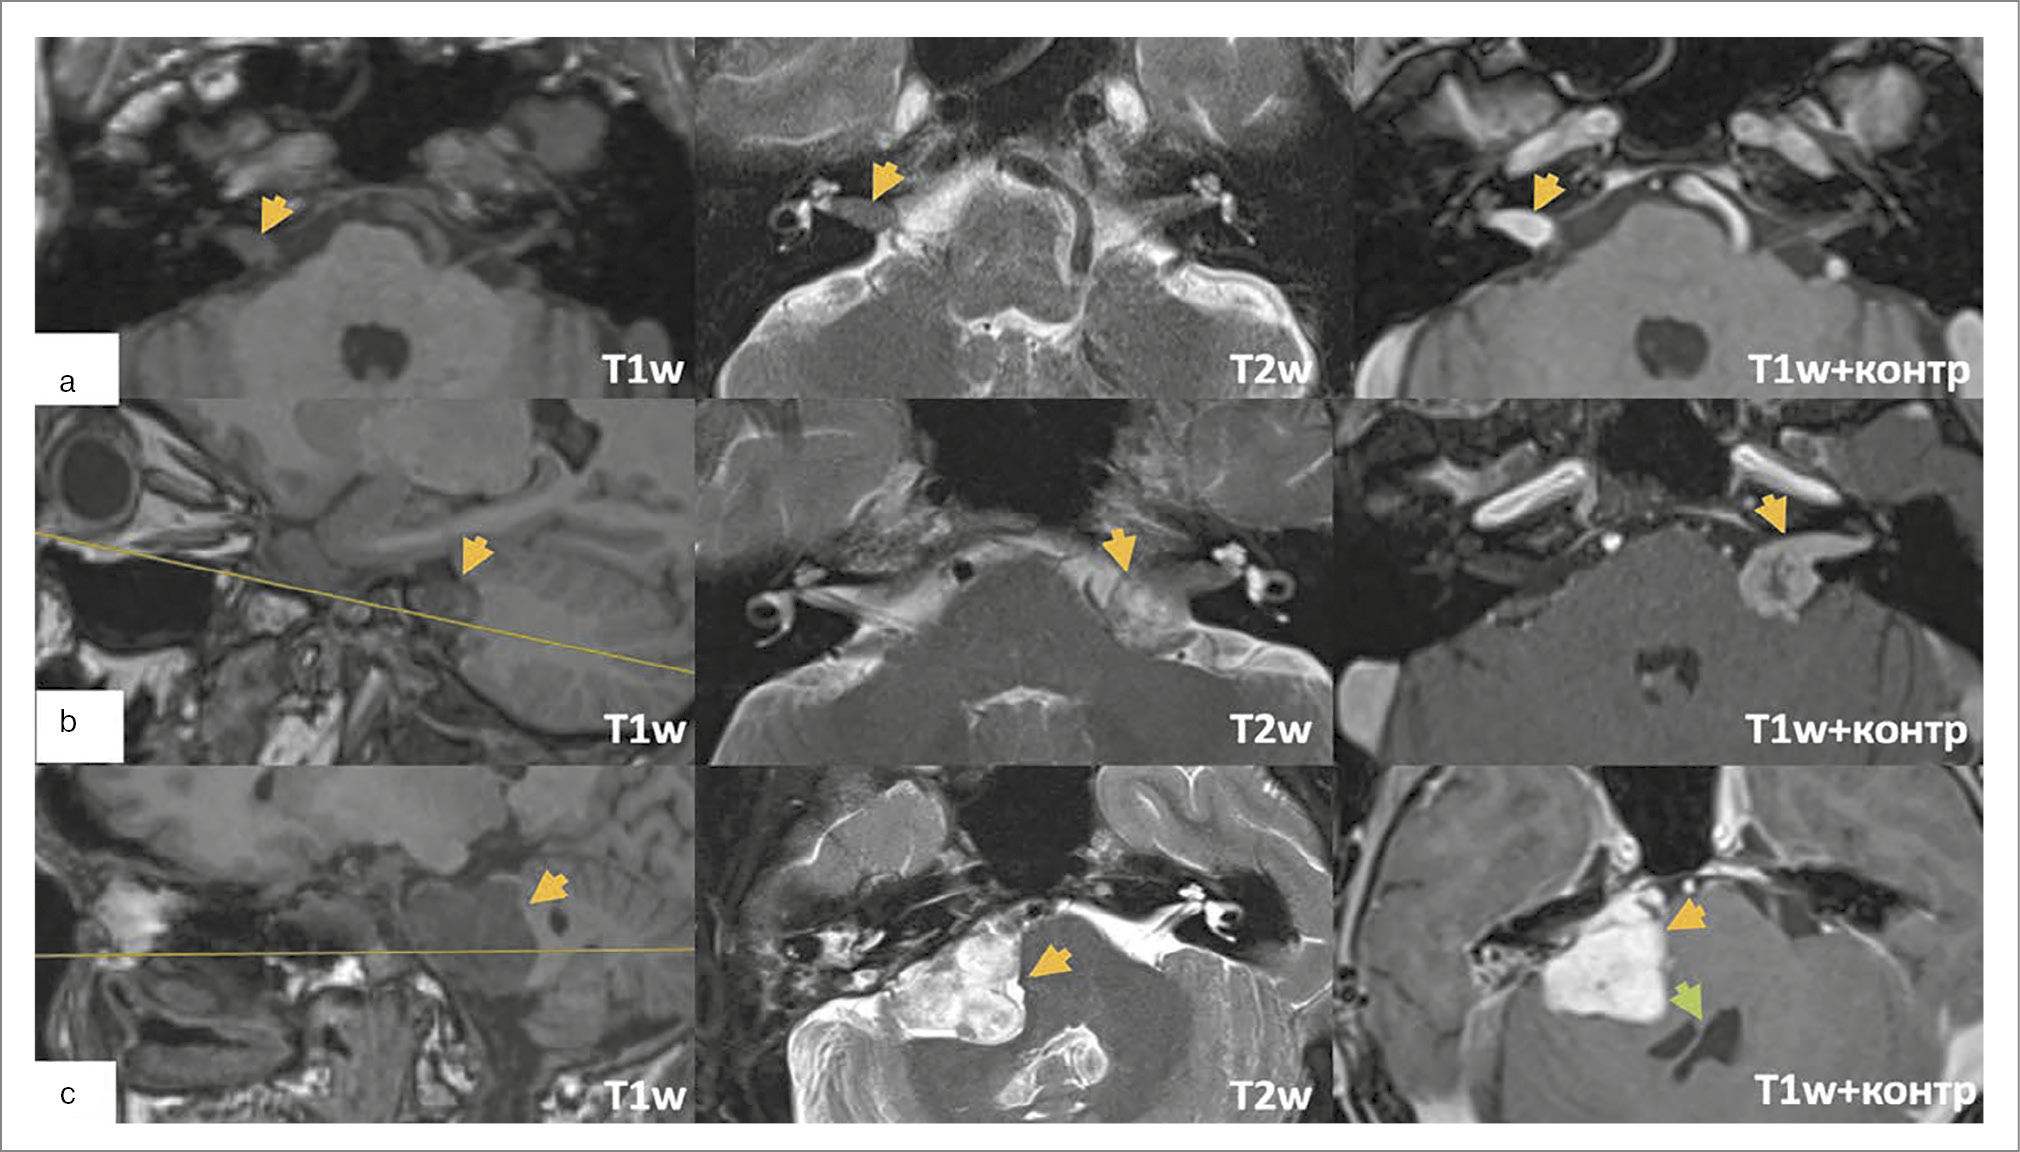

Ведущие методы исследования для установки диагноза – КТ височных костей и МРТ головного мозга. По КТ-исследованиям оценивается локализация процесса в структуре височной кости и латерального основания черепа, определяется хирургическая тактика. На данных КТ основаны наиболее актуальные современные классификации холестеатомы ПВК M. Sanna и D. Moffat и соав. [33, 36]. Холестеатома ПВК имеет тенденцию к агрессивному разрушению костных структур, может одновременно поражать несколько отделов височной кости и распространяться по супра-/инфралабиринтному ячеистому тракту к внутренней сонной артерии, верхушке пирамиды, клиновидной пазухе, в исключительно редких случаях – носоглотке; сзади к задней черепной ямке (ЗЧЯ) и сигмовидному синусу; медиально может доходить до основания ВСП и ската; вниз до яремного отверстия, канала подъязычного нерва, мыщелка затылочной кости [37]. Изолированное развитие холестеатомы в ВСП встречается редко, а разрушение стенок ВСП не указывается в классификациях, между тем несет в себе ключевое понимание о типе необходимого доступа, достаточного для санации и определения методики закрытия послеоперационной полости. Для более детальной оценки вовлеченных в патологический процесс анатомических структур, в том числе ВСП, разработана оценочная шкала CLIF (APO) [38].

Исследования МРТ производятся в стандартных режимах (Т1 – гипоинтенсивный сигнал, Т2 – гиперинтенсивный), они дополняют КТ в ходе дифференциальной диагностики. Большое значение имеет non-EPI (В1000) DWI – последовательность, высокоспецифичная для холестеатомы, играет большую роль в определении рецидивов, особенно при закрытых техниках (облитерация послеоперационной полости и закрытие наружного слухового прохода cul-de-sac); рис. 2. В случае протяженного контакта холестеатомы с магистральными сосудами и возможной необходимости перекрытия просвета сигмовидного синуса необходимо проведение МРТ с внутривенным контрастированием либо в режимах MPА (ToF, PC, 4D), чтобы оценить достаточность венозного оттока по контрлатеральной стороне [21].

Рис. 2. Исследования пациентов с холестеатомой ПВК, разрушающей ВСП: а – врожденная супралабиринтная холестеатома, локализующаяся в области дна ВСП; b – рецидив врожденной холестеатомы ПВК в области ВСП.

Одни из первых симптомов, характерных для холестеатомы ПВК с разрушением ВСП, – снижение слуха и функции мимической мускулатуры на стороне поражения. Холестеатома сдавливает прилежащие ЧМН, вызывая локальную демиелинизацию. При распространении процесса во внутреннее ухо часто развивается глухота.

К методам диагностики относятся исследования КТ и МРТ (рис. 3). В отличие от ВШ, большинство менингиом топографически исходят из задней поверхности пирамиды и отличаются широким основанием прикрепления. На КТ-срезах можно выявить участки гиперостоза прилегающей кости и кальцификаты в структуре опухоли. На МРТ в Т1-режиме ВШ и менингиомы изоинтенсивны либо слегка гипоинтенсивны. На Т2-взвешенных изображениях ВШ чаще гиперинтенсивны, в то время как менингиомы – изоинтенсивны [43–47]. Менингиомы можно отличить от шванномы также по наличию неровных границ, неравномерно накапливающих контраст. Кроме того, один из наиболее характерных симптомов – симптом «хвоста» твердой мозговой оболочки после внутривенного введения контраста.

Рис. 3. Исследования пациентов с менингиомой ВСП: а – интраканальная менингиома; b – интраканальная менингиома с распространением в ММЦ. У пациента в анамнезе стереотаксическое лечение на аппарате «Гамма-нож». На T2W МР-последовательностях видно неоднородное строение опухоли в центральных отделах, гипоинтенсивный сигнал.

При изолированной интраканальной локализации отличить менингиому от ВШ на предоперационном этапе чрезвычайно трудно. Фактически в 75–90% зарегистрированных случаев интраканальных менингиом предварительный диагноз был ВШ [43, 48]. Один из ведущих диагностических факторов – форма опухоли в ММЦ: при менингиомах обычно имеется широкое основание, а при ВШ – сферическая форма (симптом «мороженого»). K. Asaoka и соавт. ретроспективно отметили, что для менингиомы также характерна выраженная тенденция инвазии твердой мозговой оболочки и костных отделов дна ВСП [40]. Также описано распространение менингиом по волокнам преддверно-улиткового нерва в улитку, преддверие и ампулы полукружных каналов [49].